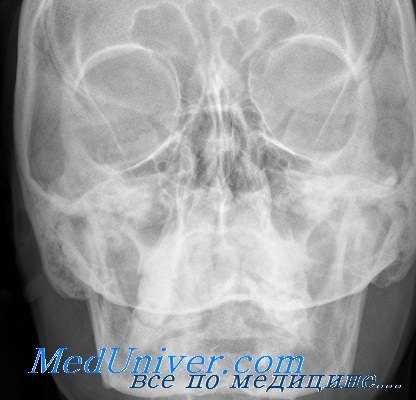

Диагностика опухолей орбиты — один из наиболее трудных разделов офтальмологии. Методами исследования являются рентгенография, при которой можно отметить истончение или разрушение стенок, увеличение размеров и затемнение пораженной орбиты, компьютерная томография, показывающая наличие опухоли, локализацию и протяженность, орбитография, основанная на рентгенологическом контрастировании орбиты, венография, термография орбиты, каротидная ангиография, В-метод эхографии (сканирование). При сосудистых поражениях орбиты и подозрении на злокачественную опухоль противопоказан метод орбитографии. Для определения злокачественности новообразования применяют радионуклеидное исследование с радиоактивным фосфором — 32 Р, йодом — 125 J и 131 J, стронцием — 85 Sr и др. Однако метод не точен, т.к. некоторые доброкачественные новообразования и псевдоопухоли орбиты могут накапливать изотоп, подобно злокачественным новообразованиям.

При рентгеновском исследовании в первый период развития новообразования отмечается затемнение пораженной глазницы, затем увеличение ее размеров, истончение ее стенок, узуры, иногда гиперостоз кости. Наличие в области глазницы тромбированных сосудов помогает диагнозу. Наиболее точный диагноз помогает поставить компьютерная томография с контрастированием, а также ультразвуковое сканирование.

Течение остеомы может осложниться эмпиемой придаточной пазухи с последующим развитием субпериостального абсцесса, абсцесса мозга, менингита. Остеомы могут прорастать из пазух не только в орбиту, но и в интракраниальную полость. Решающим в диагностике является рентгеновское исследование. На рентгенограммах определяется четкая тень, по интенсивности напоминающая костную ткань. Размеры остеом разные — от малых, величиной с горошину, где лучше применение компьютерной томографии, до огромных, занимающих соответствующую пазуху и полость глазницы.

Таким образом, все изложенное выше с несомненностью указывает на то, что на основании одних только клинических признаков нельзя с полной уверенностью решить вопрос о наличии опухоли глазницы и тем более о тех изменениях, которые происходят в полости глазницы в связи с ростом опухоли. Здесь-то значительную помощь клиницисту может оказать рентгенологический метод исследования. С помощью такого исследования в ряде случаев удается не только уточнить диагноз и выяснить причину экзофталма, но также определить характер и структуру опухоли. Такой метод исследования позволяет также с большой точностью установить место исхода опухоли, направление ее роста и наличие прорастания в смежную область.

Обследование больных с опухолью глазницы. Крайне полезно провести рентгенографическое и томографическое обследование глазницы, в результате которого можно будет сделать заключение о состоянии глазницы и зрительного канала.

При проведении КТ это заключение может быть детализировано, поскольку будет получена информация о локализации, размере и степени распространения опухоли в пределах (и вне пределов) глазницы. При этом также получают сведения о степени эрозии кости и поражения мягких тканей. Ультразвуковые исследования могут помочь быстро обнаружить опухоль. По возможности следует проводить биопсию, однако она сопряжена с риском диссеминации опухоли, возникновения геморрагии и развития слепоты. При наличии инкапсулированной опухоли ее лучше всего удалить.